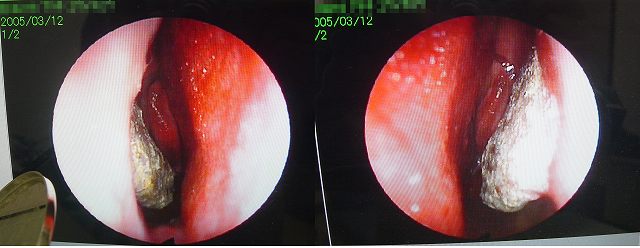

アレルギー性鼻炎には、季節性アレルギー性鼻炎(花粉症)と通年性アレルギー性鼻炎があり、 下鼻甲介粘膜が腫れる のは共通していますが、粘膜の色合いは異なっていて、 季節性アレルギー性鼻炎(花粉症)では、粘膜は赤く腫れる のに対し、 通年性アレルギー性鼻炎の粘膜は蒼白です。出典:鼻アレルギー診療ガイドライン通年性鼻炎と花粉症年版(改訂第9版):p26, 〇写真提供:NPO花粉情報協会 事務局長 佐橋紀男先生 出典:花粉学辞典(新装版)より(一部改変) 編集者 日本花粉学会 08年 「アレルシャット」は 鼻の内側に1回塗るだけ で 花粉を約4時間ブロック してくれるという、透明で粘着性の高いクリーム。 1日4回の使用で約30日分入っているので、1本で1カ月十分使